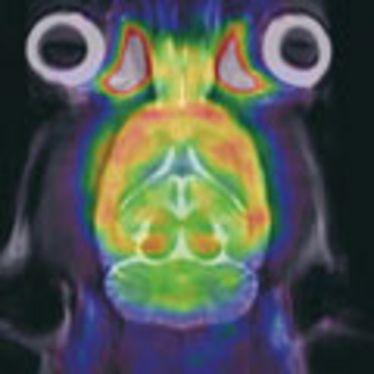

Small Animal Imaging Workshop 2011

Small Animal Imaging Workshop 2011

Small Animal Imaging Workshop

Small Animal Imaging Workshop